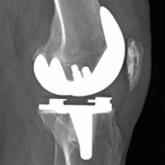

Difficult-to-Detect Low-Grade Infections Responsible for Poor Outcomes in Total Knee Arthroplasty

In this article, we present the case of a patient with a stiff, painful knee after total knee arthroplasty, and with erythrocyte sedimentation...